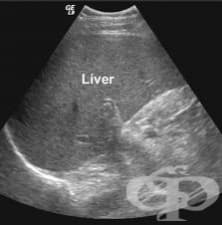

АКЦЕНТИ ОТ РУБРИКА УЛТРАЗВУКОВО ИЗСЛЕДВАНЕ (ЕХОГРАФИЯ)

АКТУАЛНО ОТ РУБРИКА УЛТРАЗВУКОВО ИЗСЛЕДВАНЕ (ЕХОГРАФИЯ)